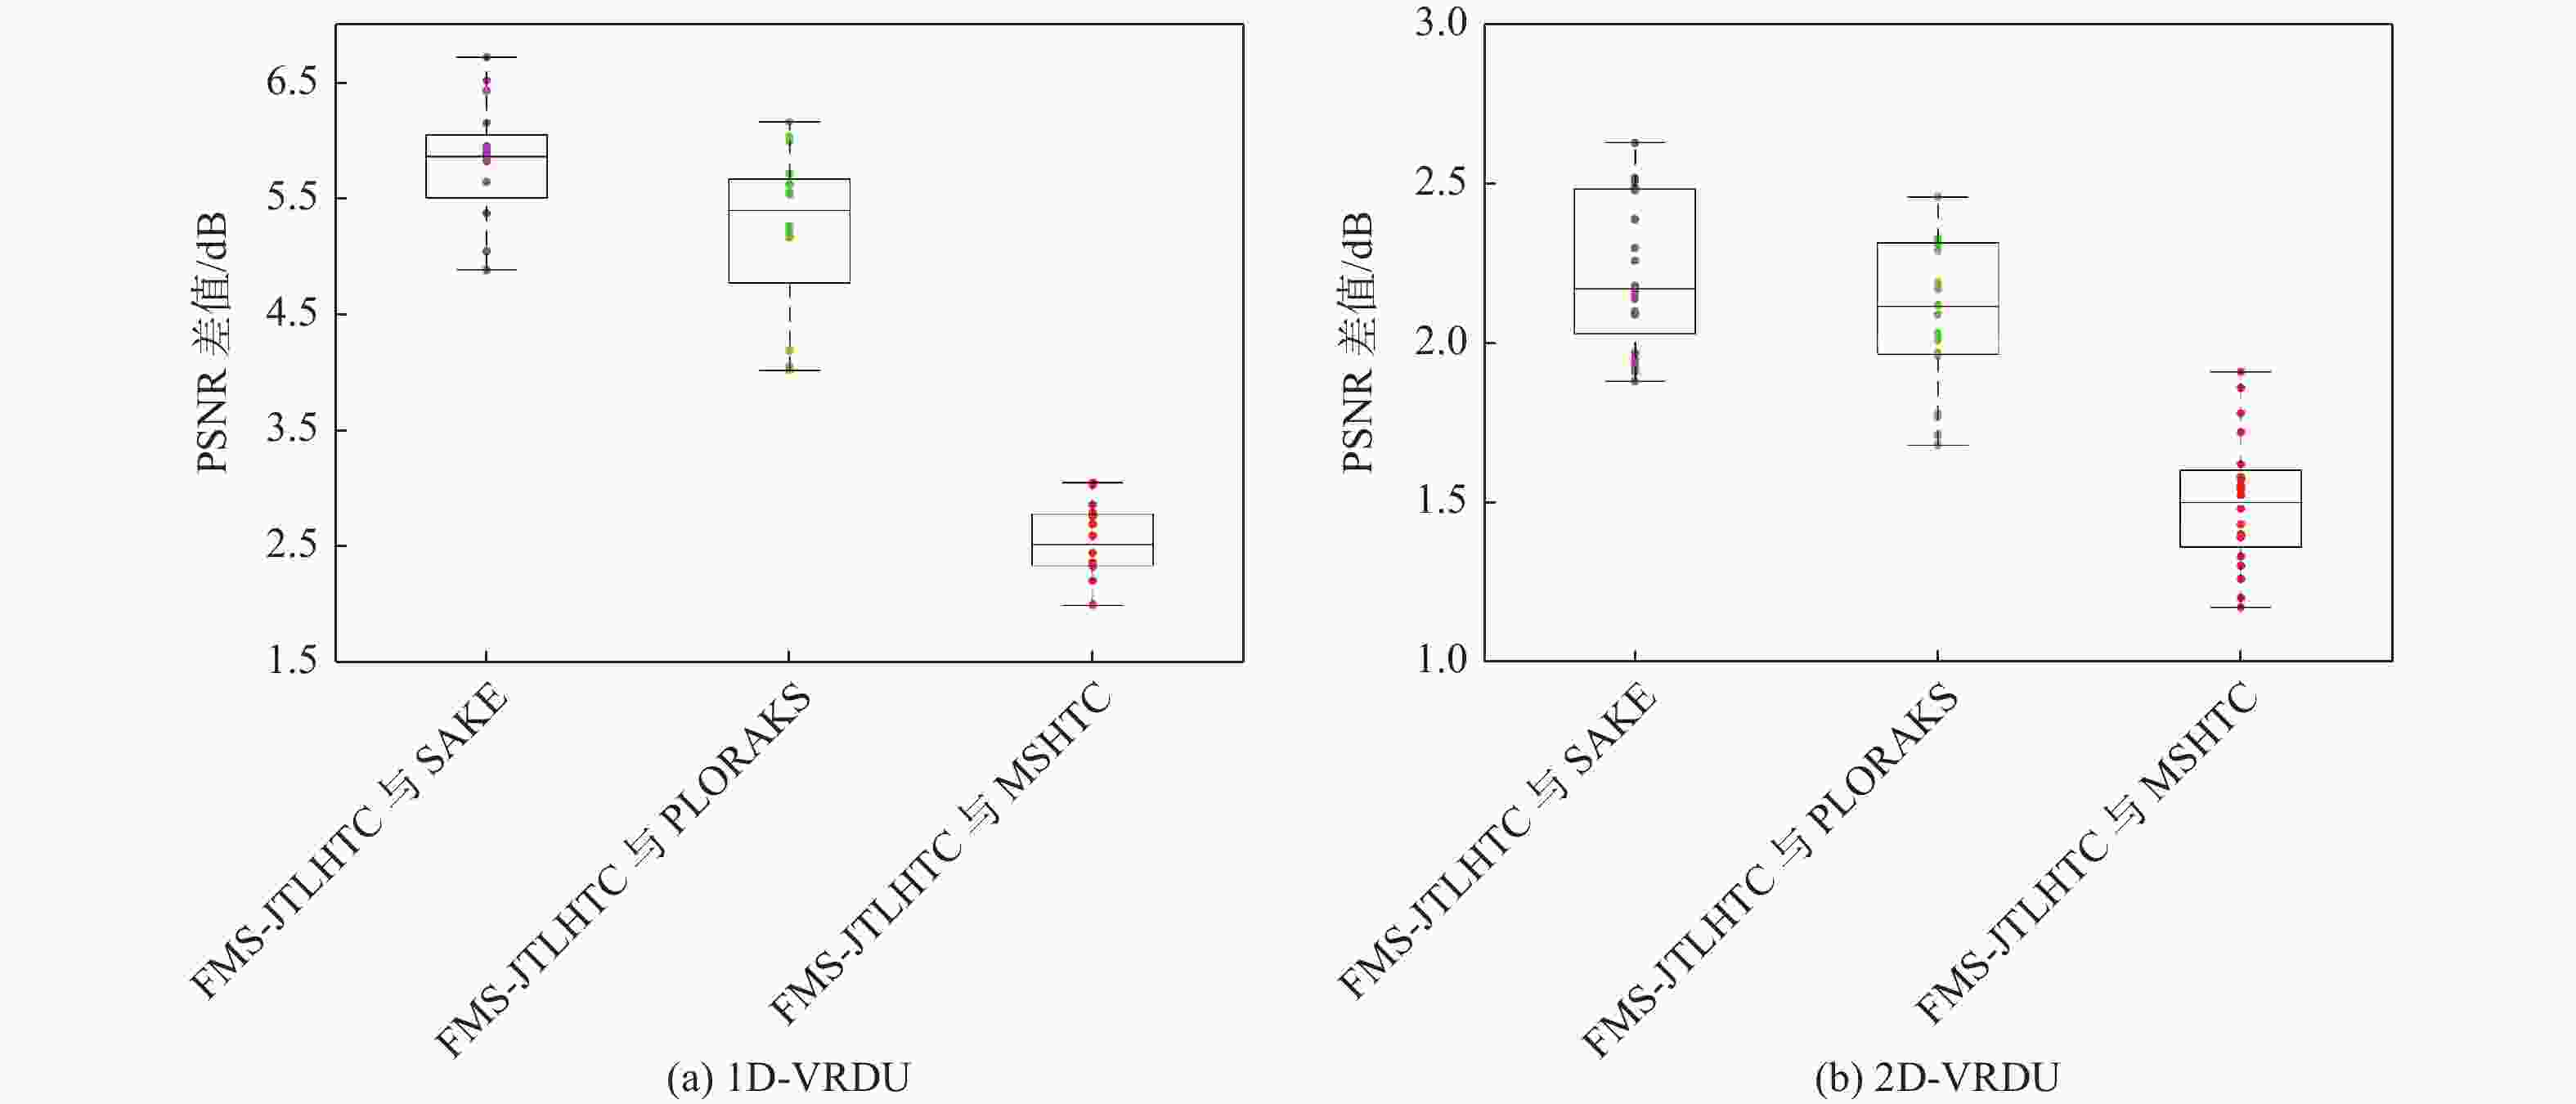

二维(2D)多切片磁共振数据在相邻切片之间具有高度的相关性,通过利用切片间的冗余性能够重建出更高质量的切片图像,但由于硬件条件的限制,2D多切片磁共振成像(MRI)需要耗费大量时间。为提高2D多切片磁共振图像的重建质量和重建速度,将联合稀疏变换学习正则项引入到多切片Hankel张量完成(MS-HTC)模型中,提出一种快速2D多切片磁共振成像重建(FMS-JTLHTC)算法。该算法使用交替方向乘子法对目标问题进行求解;引入快速迭代收缩阈值法加快收敛,并使用图形处理器对算法进行加速。使用4组脑部数据集在2种不同采样模式下进行实验,结果表明:FMS-JTLHTC算法的峰值信噪比(PSNR)相较于同时自动校准和K空间估计(SAKE)算法、并行成像数据的局部K空间领域的低秩建模(PLORAKS)算法和MS-HTC算法分别平均提高了4.04 dB、3.67 dB和2.07 dB,而且重建速度相比MS-HTC算法提高了14倍。

Abstract:Due to the significant correlation between neighboring slices in two-dimensional (2D) multi-slice magnetic resonance data, higher quality slice pictures can be reconstructed by taking use of the redundancy between slices. However, 2D multi-slice magnetic resonance imaging requires an amount of time. To improve the reconstruction quality and speed of 2D multi-slice (MRI) images, proposes a fast 2D multi-slice MRI reconstruction (FMS-JTLHTC) algorithm, which introduces the joint transform learning regular term into the multi-slice hankel tensor completion (MS-HTC) model. Prior to introducing the fast iterative shrinkage-thresholding procedure to accelerate convergence and utilize the graphics processing unit to speed up the procedure, the alternating direction method of multipliers is used to solve the objective issue. Experiments using four brain datasets in two different sampling modes show that the peak signal-to-noise ratio (PSNR) of the FMS-JTLHTC algorithm is improved by an average of 4.04 dB, 3.67 dB, and 2.07 dB compared to the simultaneous atuo-calibrating and K-space estimation (SAKE), low-rank modeling of local K-space neighborhoods with parallel imaging data (PLORAKS) and MS-HTC algorithms, respectively, the reconstruction speed is improved by a factor of 14 compared to the MS-HTC algorithm.